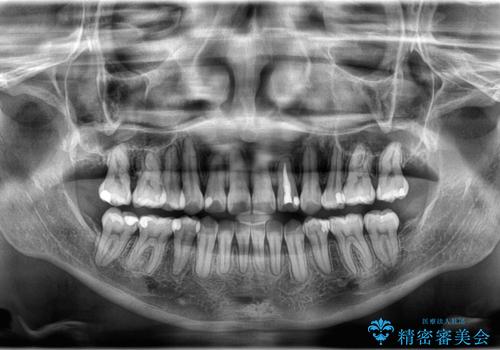

- 「歯のでこぼこを治したい」を主訴に来院された患者様です。 上下ともに、歯のでこぼこが強く、上下左右4の抜歯をし、ワイヤー矯正で治療を行いました。

かなり綺麗に並ぶ事ができ大変満足していただけました。

叢生量がかなり多かったのですが、歯肉退縮も失活歯も無くとても綺麗な歯並びになりました。